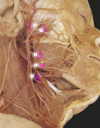

Q

Which arteries do the arrows point to? [1]

A

Lenticulostiate arteries